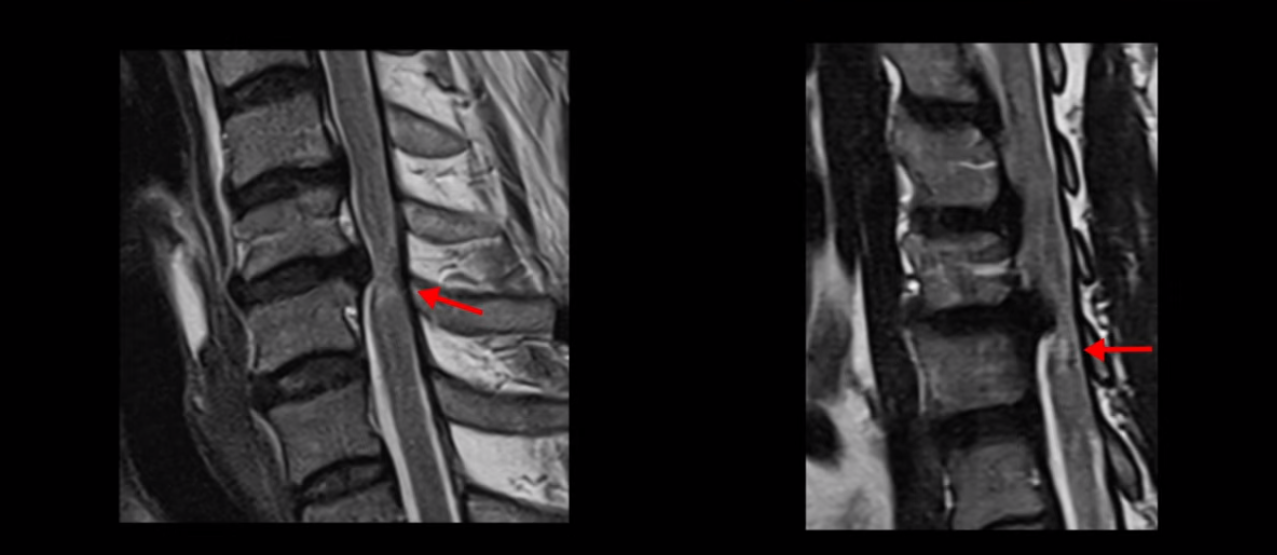

MRI 보면 무려 3마디의 허리 뒤쪽, 후궁 뼈 한쪽을 거의 다 뜯어내고

황색 인대를 대부분 다 걷어냈습니다.

문제는 이 허리 협착이 양손과 양쪽 다리 힘 빠짐의 원인이 아니었기에 수술 후에도 증상이 전혀 좋아지질 않습니다. 그나마 다행인 건 허리 여러 마디를 수술하면서도 나사를 안 박은 겁니다. 수술로 인해 허리 여러 마디에 손상이 생기니까 걷기가 더 어려워져서 결국 저희 병원에 오실 때는 휠체어를 타고 오셨습니다.